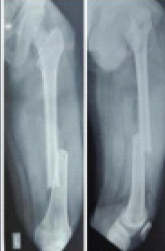

Outcome Assessment of Femoral Shaft Fractures Managed by Nailing and Derotation Plating

Ismail Pandor , Abhishek Sharma , Aamir Shahzad , Fahim Ali , Alim Shaikh , Anshuraj Jagdale

………………………………p.261-265